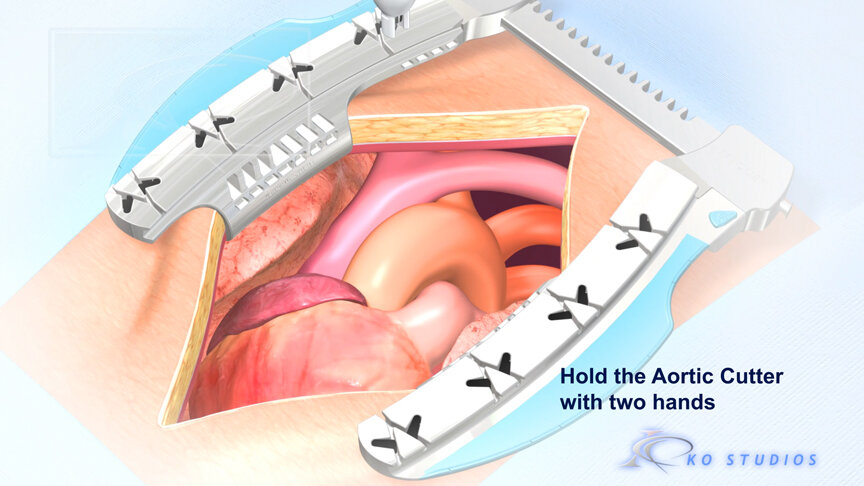

EnCompass F2 Device for cerebral embolic protection system in TAVR procedures

EnCompass Technologies

EnCompass’ F2 filter has pores small enough to block most emboli to the brain while preserving blood flow. During the TAVR procedure, 360-degree wall apposition of the filter in the aortic arch prevents migration. The filter, attached to a self-expanding, nitinol stent, is easy to insert, deploy and retrieve, according to the company. Copyright ©2021 KO Studios.